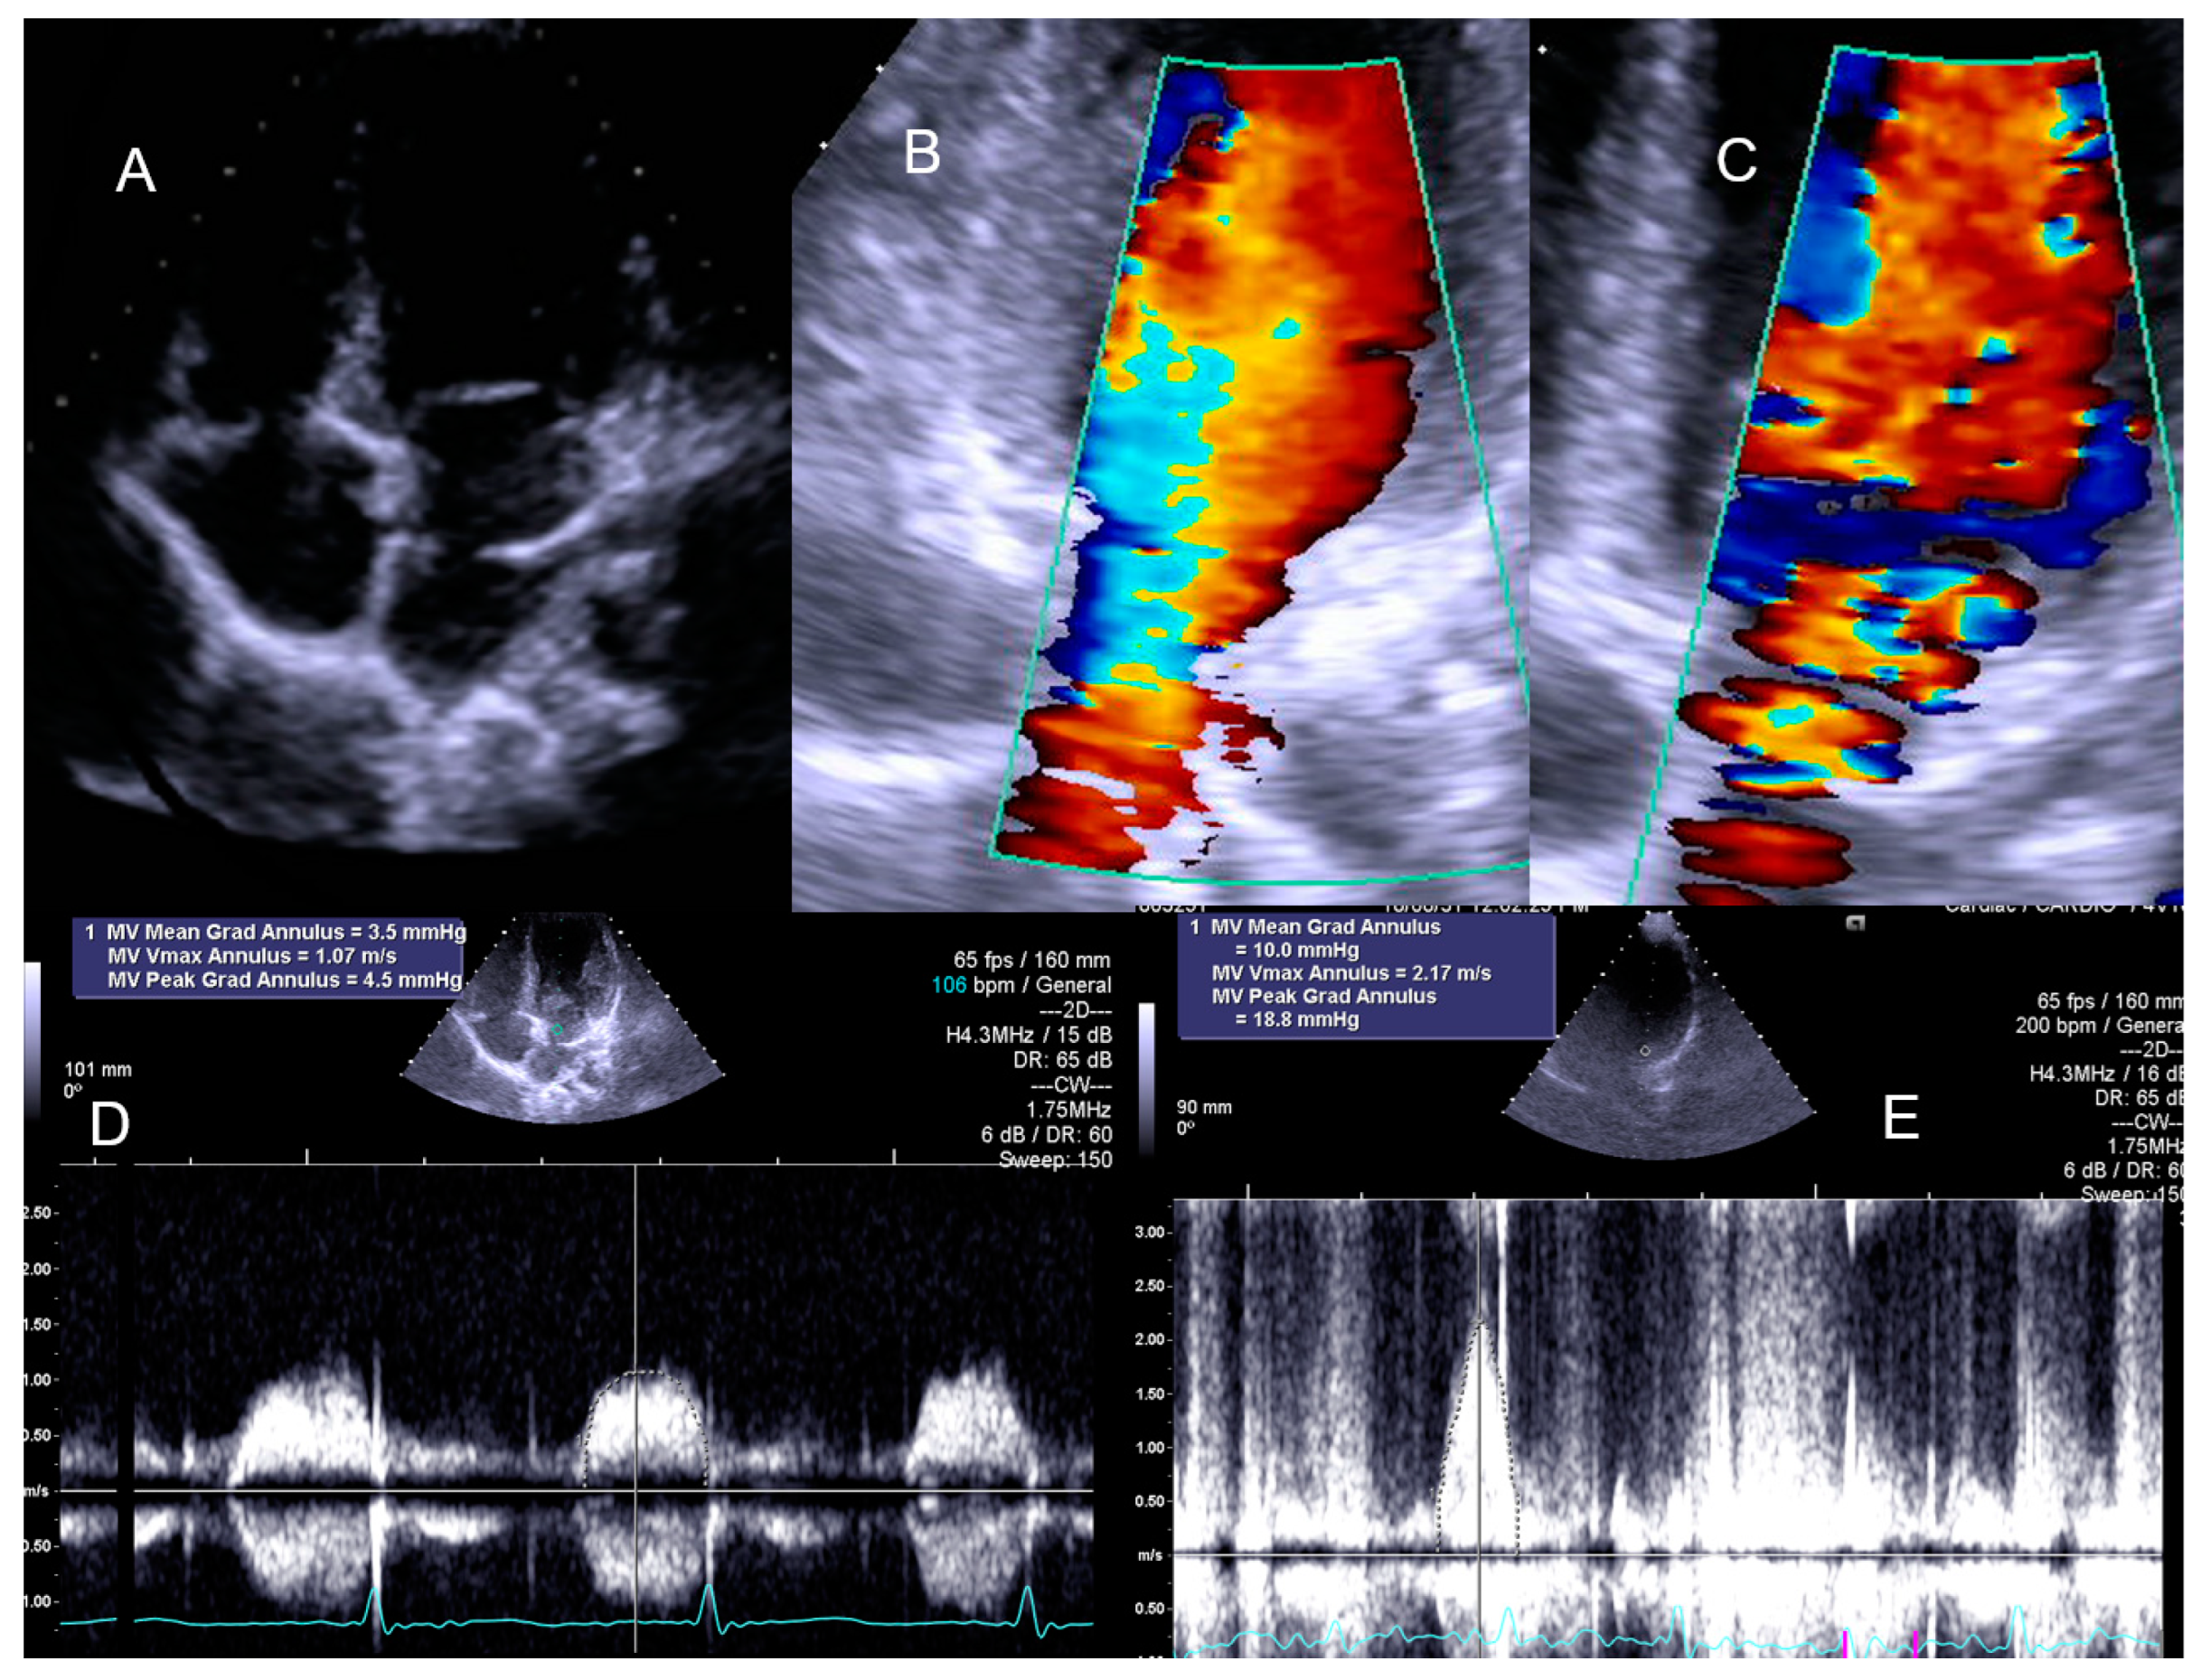

- Cotrim, C.; Palinkas, E.D.; Cotrim, N. The Importance of Left Ventricular Outflow Tract and Mid-Ventricular Gradients in Stress Echocardiography: A Narrative Review. J. Clin. Med. 2023, 12, 5292. [Google Scholar] [CrossRef] [PubMed]

- Citro, R.; Bursi, F.; Bellino, M.; Picano, E. The Role of Stress Echocardiography in Valvular Heart Disease. Curr. Cardiol. Rep. 2022, 24, 1477–1485. [Google Scholar] [CrossRef]

- Picano, E.; Pierard, L.; Peteiro, J.; Djordjevic-Dikic, A.; Sade, L.E.; Cortigiani, L.; Van De Heyning, C.M.; Celutkiene, J.; Gaibazzi, N.; Ciampi, Q.; et al. The clinical use of stress echocardiography in chronic coronary syndromes and beyond coronary artery disease: A clinical consensus statement from the European Association of Cardiovascular Imaging of the ESC. Eur. Heart J. Cardiovasc. Imaging 2024, 25, e65–e90. [Google Scholar] [CrossRef]